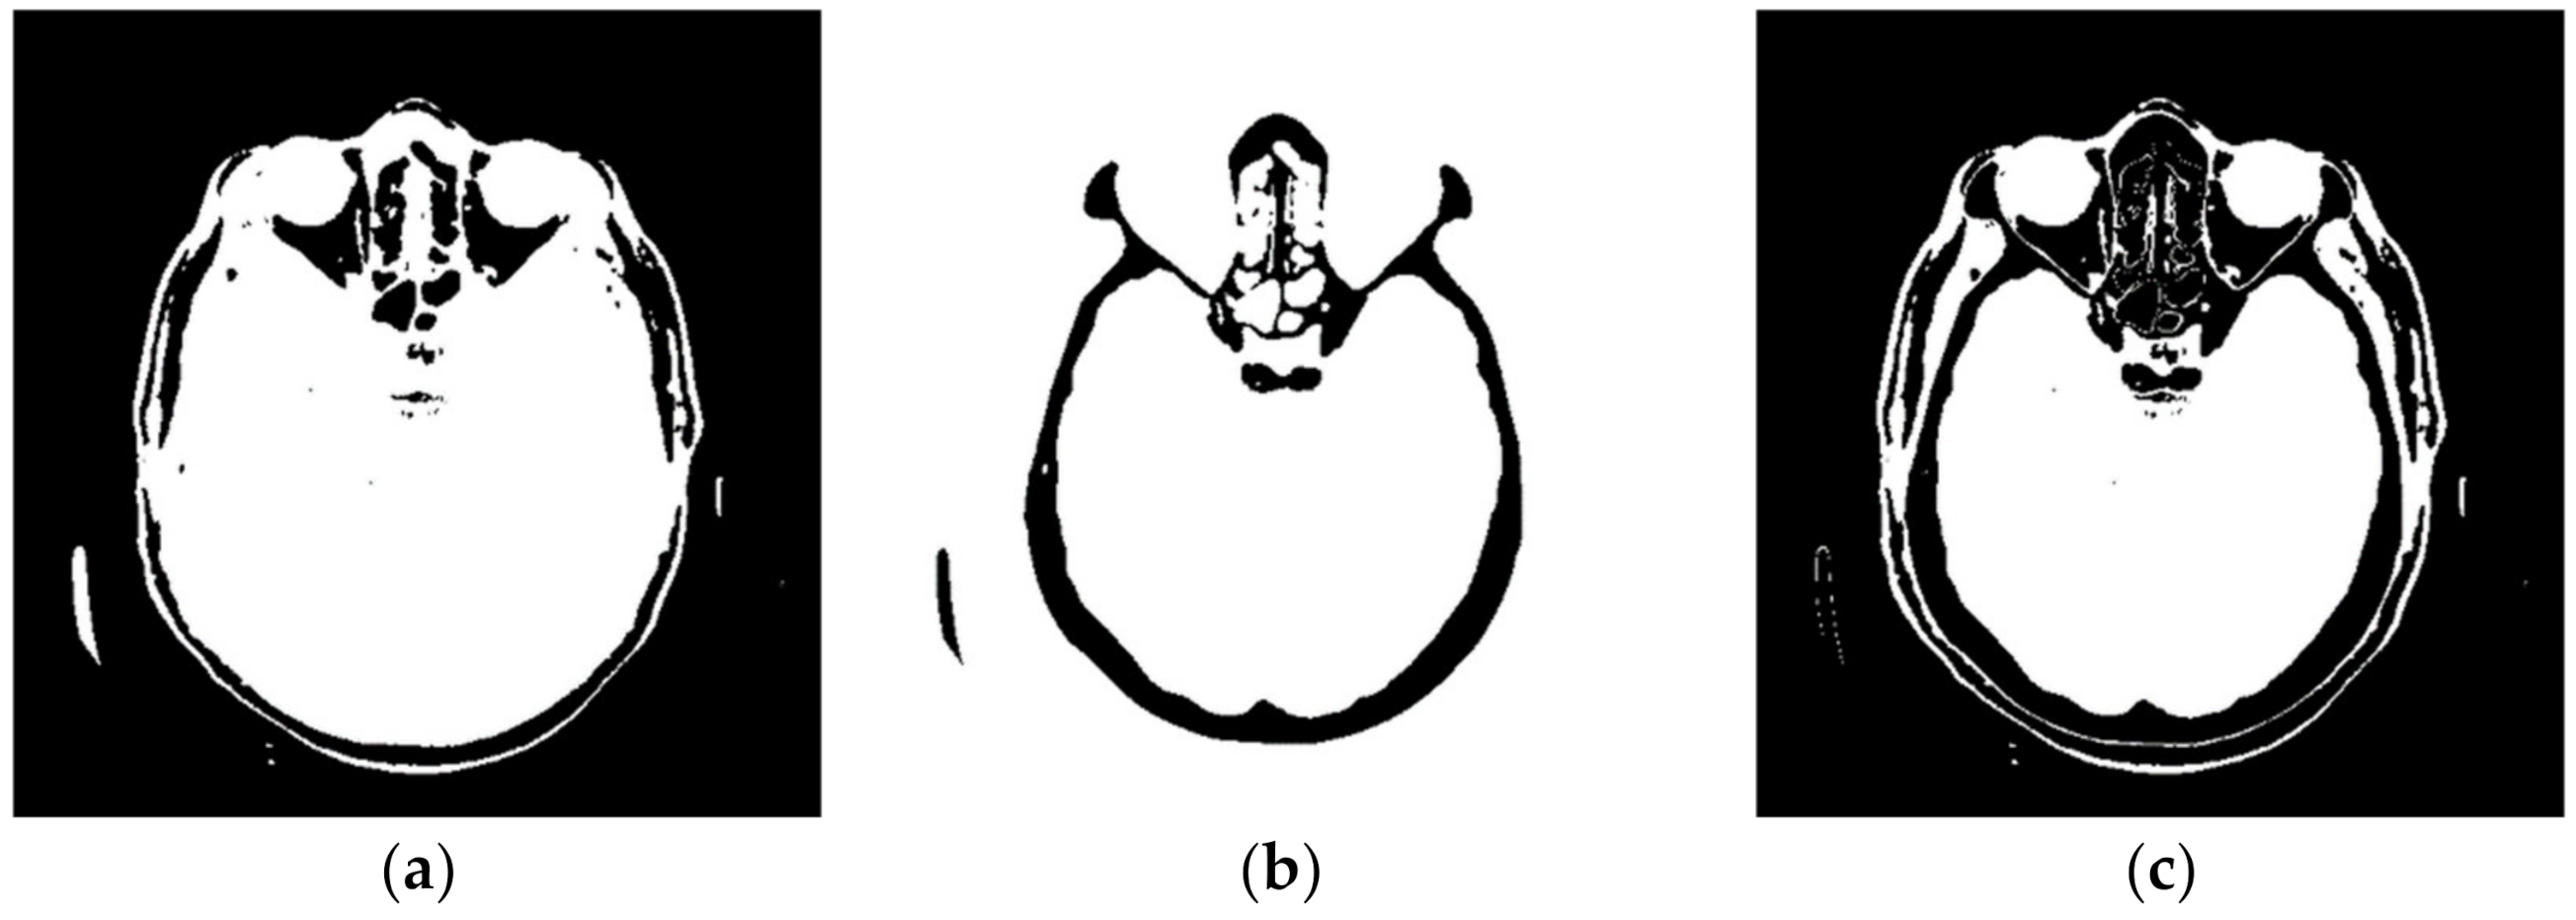

2.2. Smart Visualization Method (SVMI)

3.1. Technological Description